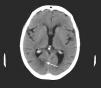

A brain CT scan showed a hypodensity in the right posterior cerebral artery (PCA) territory, affecting the calcarine sulcus (Fig. 1).